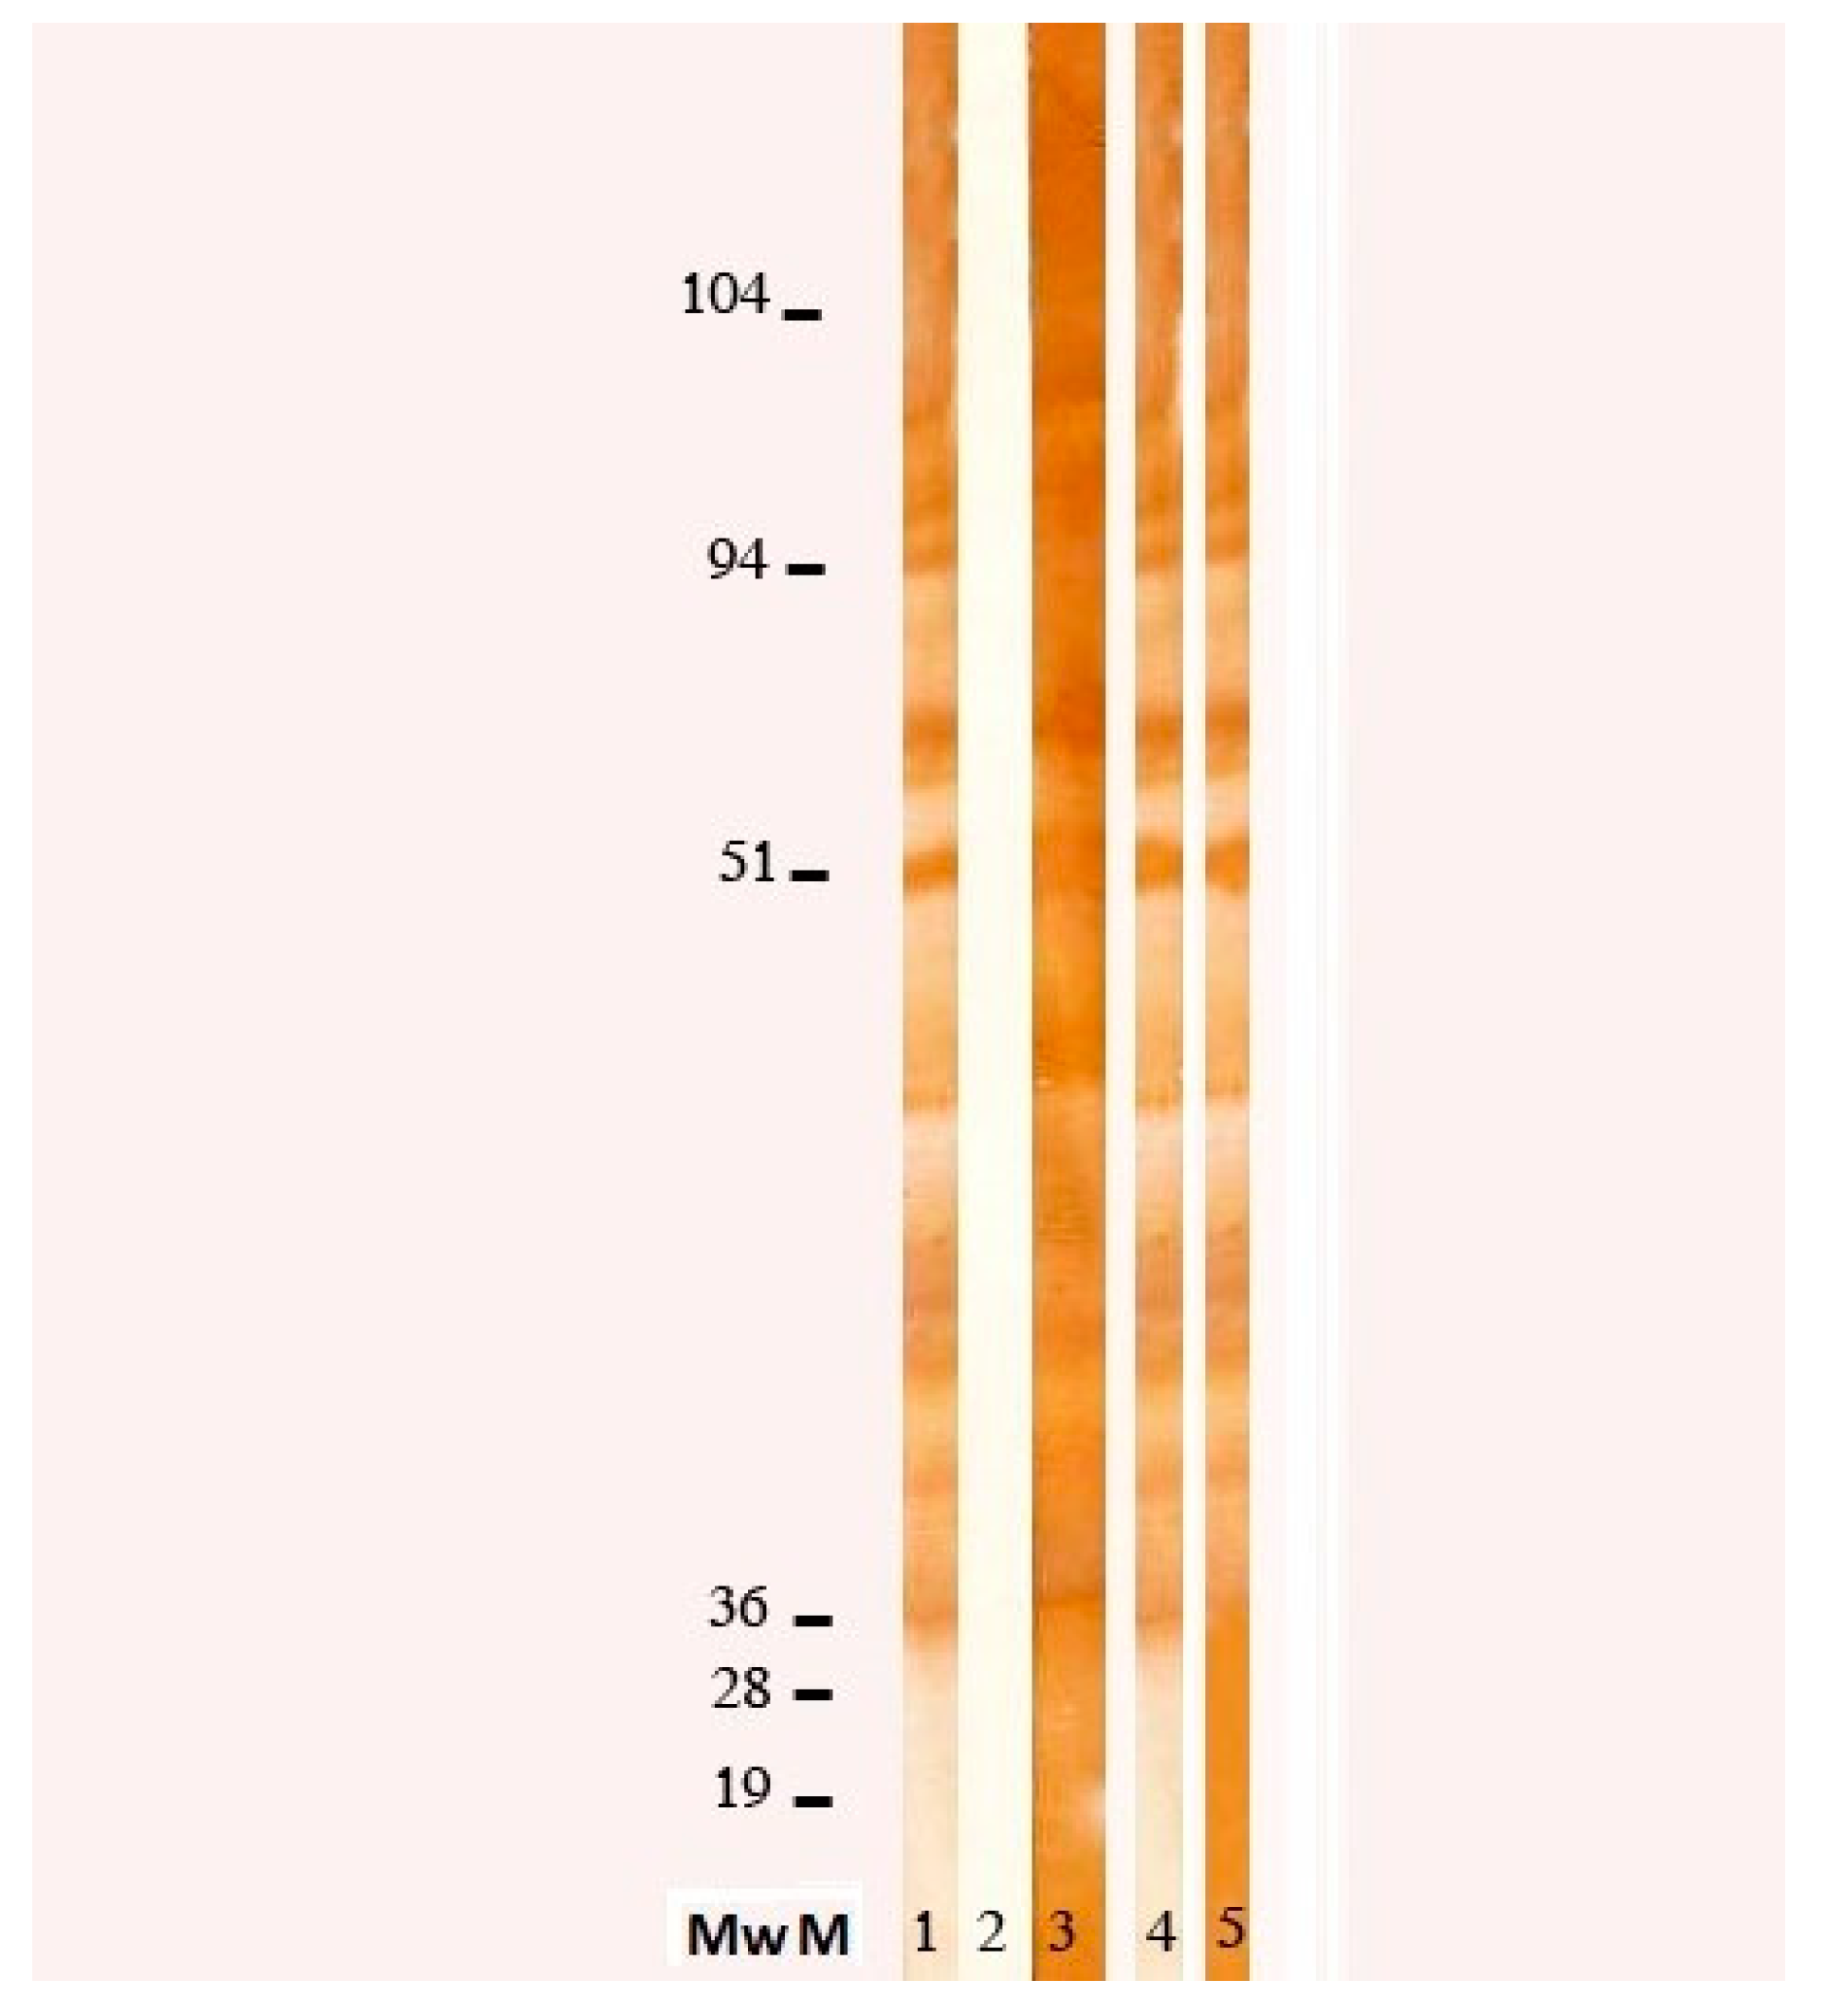

Toxocara canis (Nova Tec, srl, Dietzenbach, Germany) revealed an elevated positivity (specificity 98.63%, sensibility 96.92%), which was confirmed by WB (see

Figure 2), allowing us to make a diagnosis of Visceral Larva migrans syndrome. Further tests showed an increase of anti-B isohemagglutinin title (1:256). To exclude central nervous system (CNS) and ocular involvement, a brain MRI and an ophthalmologic examination were performed, both resulting negative. Finally, we excluded a cardiac involvement with an echocardiography.

Toxocariasis suspicion is made considering anamnestic evaluation, signs and symptoms (which are variable due to localization of granulomas) and laboratory findings (severe eosinophilia). Diagnosis of Toxocara infection is obtained by an ELISA test, which confirm exposure to the parasite, combined with WB, which demonstrate the ongoing infection.